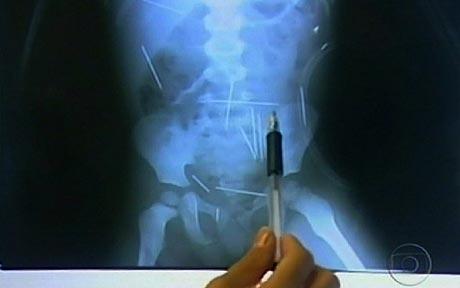

바레이라스의 한 병원 원장인 루이즈 솔토스키는 아이가 복통을 호소해 엑스레이 촬영을 한 결과, 몸에서 길이 5㎝ 가량의 바늘 수 십 개를 발견했다고 밝혔다.

의료진은 즉각 수술을 시도했지만 상황은 좋지 않았다. 일부 바늘이 폐 등의 주요 장기와 너무 가까이 있어 제거에 큰 어려움이 따른 것.

사진=동영상캡처